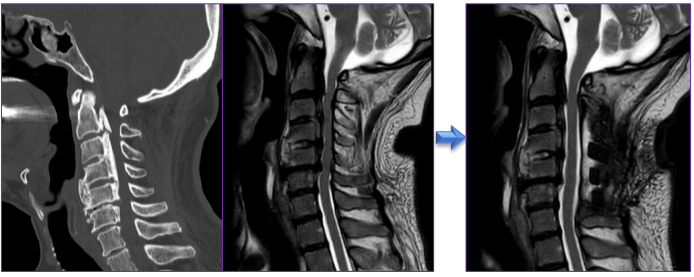

B.後ろからの手術(頚椎椎弓形成術)

首の後面の皮膚を縦切開(5~6cm)し、棘突起を露出します。棘突起を縦割し、筋肉を温存しながら椎弓を露出します。椎弓を正中で離断し、両側でヒンジを作り椎弓を折り曲げて観音開きにします。両側の椎弓間に人工椎弓を挟み込み、糸で固定します。